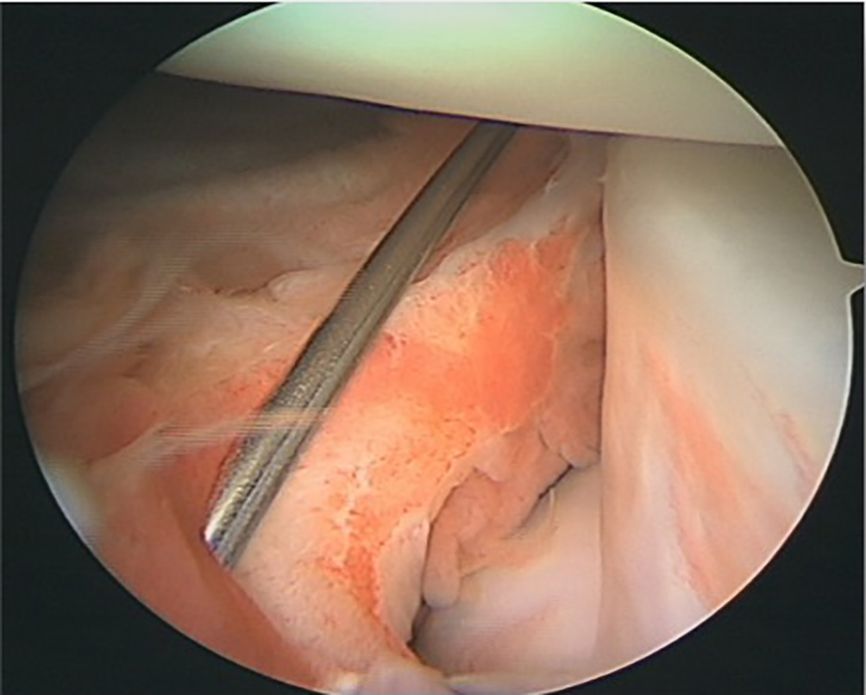

Intra-articular injuries mainly include medial or lateral meniscal injuries. More specific lesions, such as those of the medial meniscal ramp and the meniscal roots, in particular of the external meniscus, are also experienced (29,30) (Figure 7). Cartilage injuries should also not be overlooked because they are important for the long-term outcome of the knee. The prevalence of medial meniscal ramp injuries is estimated at 15.5–24% (29,31,32).

Meniscal root injuries also play a role in the rotational instability of the knee, in particular external meniscal root injuries (35,36). The prevalence of external meniscus root injuries ranges from 6.6%– 13.5% (30,37). These injuries should be diagnosed and treated simultaneously (Figure 8).